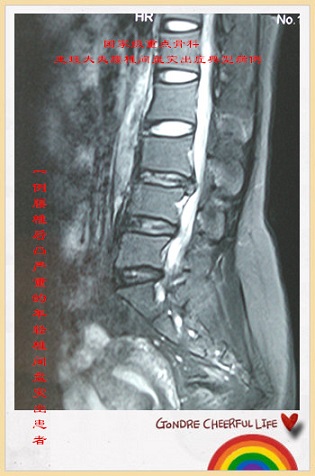

病例125:一例腰椎后凸严重的年轻椎间盘突出患者